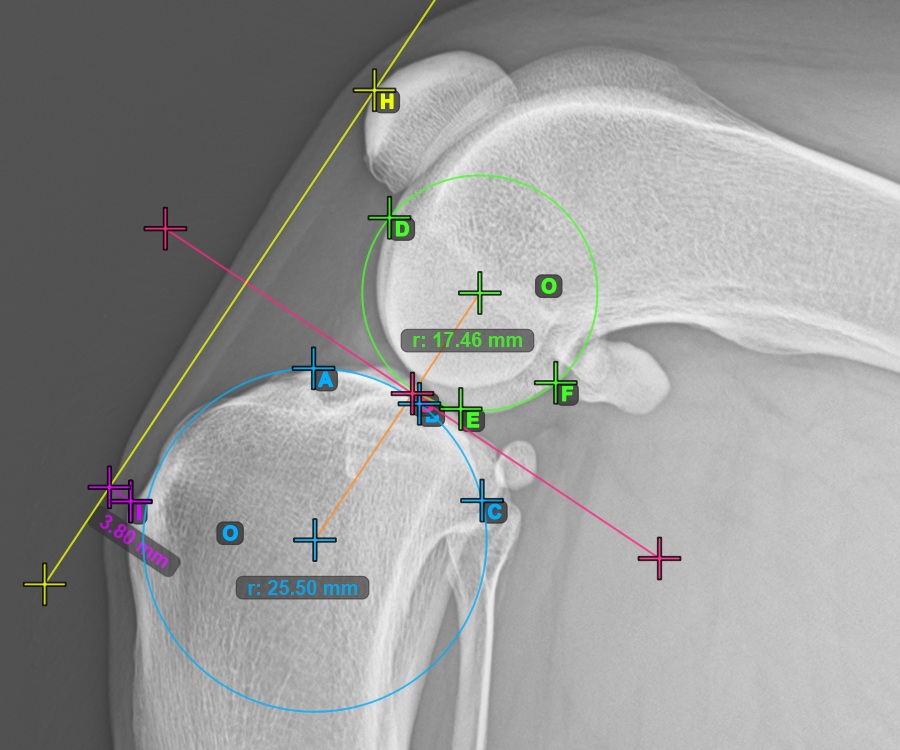

Mark one point in front of the joint on the common tangent between the two circles. A line will be drawn automatically through the marked point.

The image below represents a typical placement of the point on the common tangent between the two circles.

Start the TTA measurement procedure by marking the most cranial point of the Patella.

The image below depicts the usual placement of the most cranial point of the Patella.

To complete the TTA - 1 Condylus variant of TTA measurement procedure mark the most dorsal point of the Crista Tibiae (Tuberositas Tibiae). The distance between the Tuberositas Tibiae and the line passing along the most cranial point of the Patella is the required adjustment for the TTA procedure.

The image below depicts the usual placement of the tibial tuberosity, the most prominent point of the tibial crest.